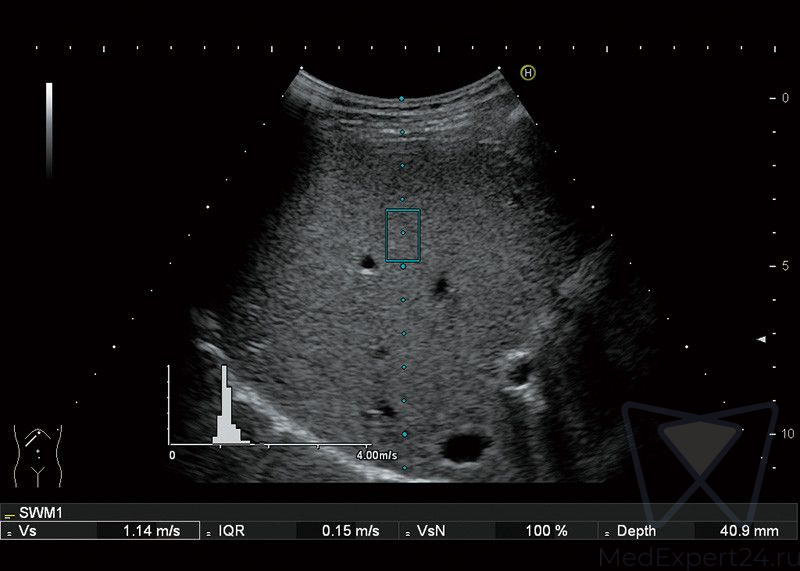

- HI-RTE эластография в режиме реального времени,